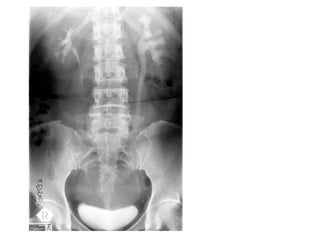

AXR/KUB- renal calculi Describe? Radio-opaque mass noted at R kidney Dx? Renal staghorn calculi Cx? Hydronephrosis/pyelo-nephrosis/-nephritis Renal failure SCC 2 other Ix? IVU (filling defect/impaired renal fx) Renal U/S (exclude hydronephrosis/hydroureter)

AXR/KUB- renal calculiDescribe? Radio-opaque mass noted at R kidney Dx? Renal staghorn calculi Cx? Hydronephrosis/pyelo-nephrosis/-nephritis Renal failure SCC 2 other Ix? IVU (filling defect/impaired renal fx) Renal U/S (exclude hydronephrosis/hydroureter)